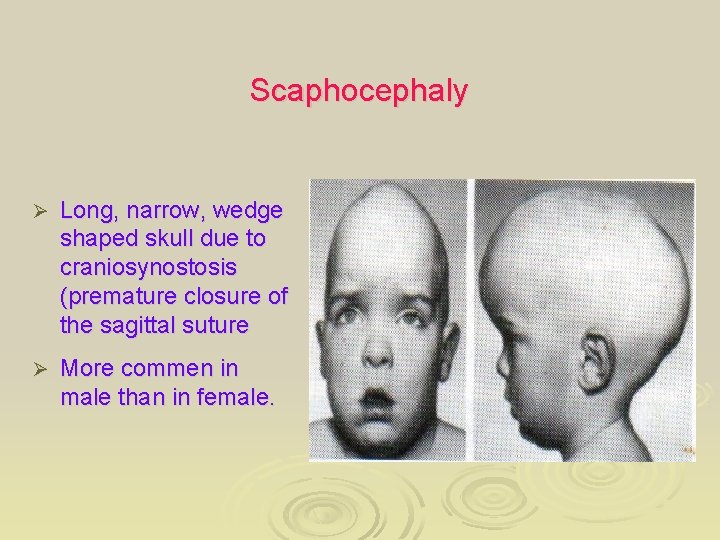

Scaphocephaly Ø Long, narrow, wedge shaped skull due to craniosynostosis (premature closure of the sagittal suture Ø More commen in male than in female.